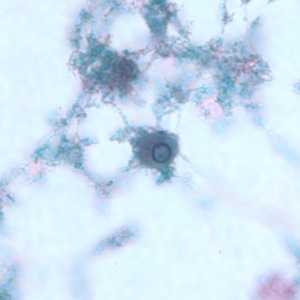

Figure A: Cysts of E. nana stained with trichrome.

Figure B: Cyst of E. nana stained with trichrome.

Figure C: Cyst of E. nana stained with trichrome.

Figure D: Cyst of E. nana stained with trichrome.